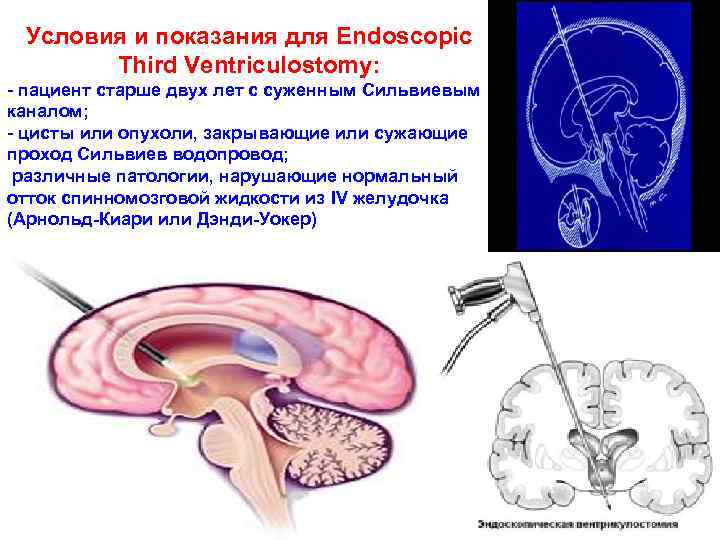

Нейроэндоскопия (Endoscopic Third Ventriculostomy) – эндоскопическое вскрытие III желудочка мозга Это относительно новая процедура, при которой производится отверстие основания III желудочка мозга. Такое хирургическое вмешательство заменяет шунтирование при окклюзионной гидроцефалии и восстанавливает ликвороциркуляцию. Тонкий эндоскопический катетер вводится в мозговую ткань (чаще всего это передняя правая часть мозга). Пройдя боковой желудочек, катетер проникает в третий через отверстие Монро. С помощью источника света и оптических волокон информация об анатомии мозга и различных новообразованиях поступает на монитор оперирующего хирурга. Специальными инструментами выполняется отверстие на дне III желудочка, позволяющее быстрый отток спинномозговой жидкости и ее циркуляцию, минуя Сильвиев водопровод 104

Условия и показания для Endoscopic Third Ventriculostomy: - пациент старше двух лет с суженным Сильвиевым каналом; - цисты или опухоли, закрывающие или сужающие проход Сильвиев водопровод; различные патологии, нарушающие нормальный отток спинномозговой жидкости из IV желудочка (Арнольд Киари или Дэнди Уокер) 105